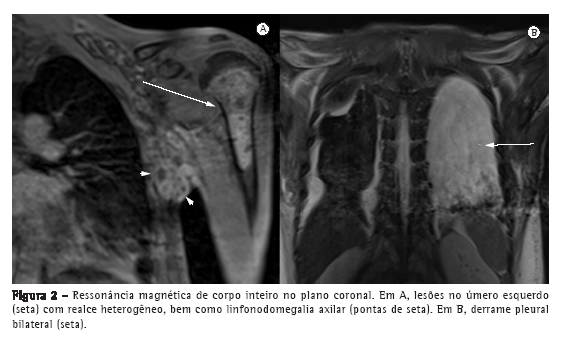

Em T1, as lesões ósseas variaram de hipointensa a isointensa, exibindo, em alguns locais, destruição do osso cortical e um extenso componente de partes moles. Em uma sequência de VIBE com gadolínio e supressão de gordura, as lesões exibiram um padrão de insuflação, com realce predominantemente nas regiões periféricas (Figuras 1B e 2A). Em uma sequência STIR, as porções centrais das lesões apresentaram sinais hiperintensos, sugerindo a presença de tecido necrótico.

A RM de corpo inteiro com sequências STIR também revelou envolvimento pleural e peritoneal, manifestando-se na forma de derrame pleural e ascite, evidenciados por um típico sinal hiperintenso (Figura 2B). Não houve outros locais de envolvimento.